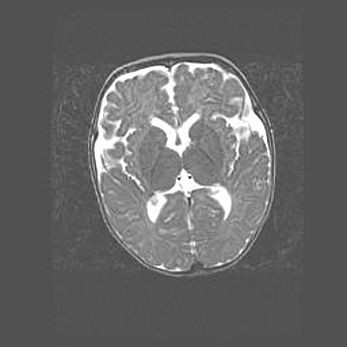

Лейкомаляция с кистозно-глиозной дегенерацией головного мозга.

Возраст: 2 месяца 25 дней

Вес: 6400 г

Окружность головы: 40 см

Срок гестации: 41 неделя

Лейкомаляцию относят к ишемически-гипоксическим повреждениям головного мозга, диагностируемым у новорожденных. При лейкомаляции в головном мозге обнаруживают очаги некроза, возникшие после тяжелой гипоксии и нарушения кровотока. В процессе морфогенеза очаги проходят три стадии: 1) развития некроза, 2) резорбции и 3) формирования глиозного рубца или кисты. Перивентрикулярная лейкомаляция (ПЛ) встречается примерно в 12% случаев среди новорожденных, обычно – у недоношенных детей, причем, частота ее зависит от массы, с которой младенец появился на свет. Наибольшее число малышей страдает лейкомаляцией, если масса при рождении 1500-2500 г.